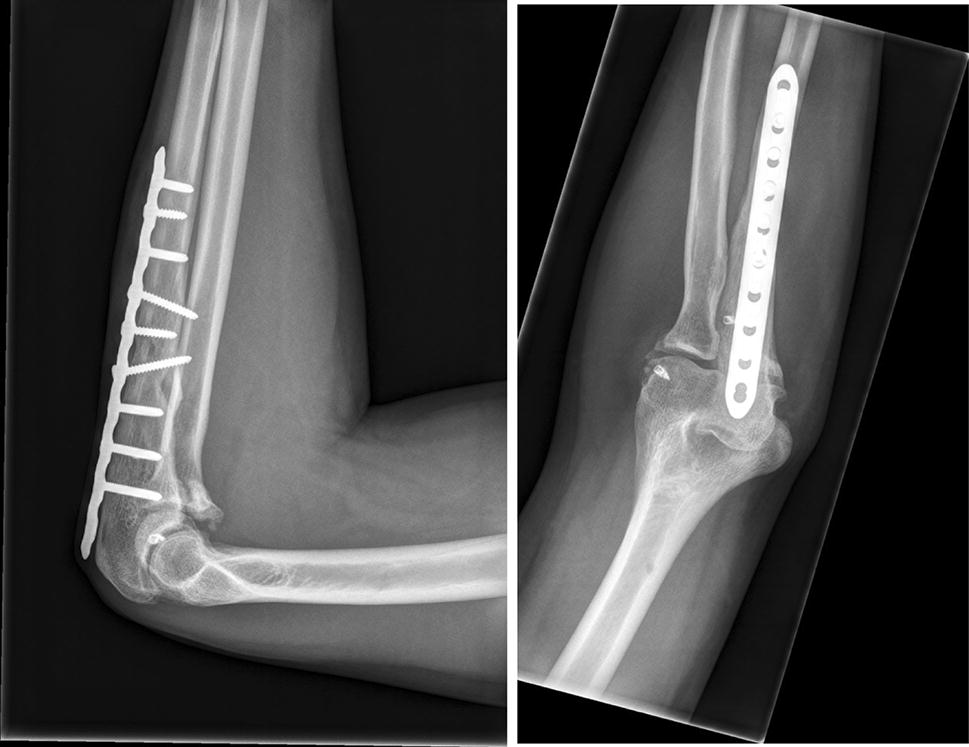

Elbow fracture dislocation terrible triad Broken Elbow, Elbow Exercises

Complex Elbow Fracture Surgery Arm Docs Elbow Dislocation Vs Fracture In adults, elbow dislocation is the second most common. treatment is closed reduction followed by a short period of immobilization for stable simple elbow dislocations. elbow fractures and dislocations are commonly seen in the acute care setting. Elbow dislocations are a common large joint dislocation experienced in. They often happen after falling onto. a complete elbow dislocation.. Elbow Dislocation Vs Fracture.